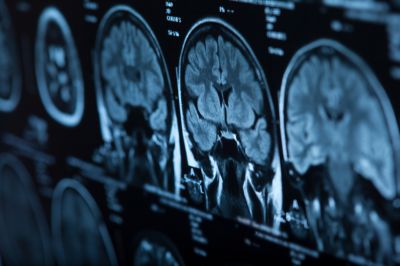

Воздействие загрязненного воздуха повышало риск развития менингиомы

Ученые из Датского института рака в Копенгагене изучили связь между загрязнением воздуха и частотой развития менингиомы. Результаты исследования опубликованы в журнале Neurology Clinical Practice.

Анализ показал, что у людей, подвергавшихся высокому воздействию загрязнителей, вероятность развития менингиомы была значительно выше. Например, каждые дополнительные 5747 ультрадисперсных частиц на кубический сантиметр увеличивали риск на 10%. Для мелкодисперсных частиц (PM2.5) риск возрастал на 21% на каждые 4 мкг/м³, для диоксида азота — на 12% на каждые 8,3 мкг/м³. Для элементарного углерода риск возрастал на 3% на каждые 0,4 мкг/м³.

Анализировали данные почти 4 млн взрослых жителей Дании, средний возраст которых составил 35 лет. За 21 год у 16 596 человек диагностировали опухоль центральной нервной системы, в том числе у 4645 участников — менингиому. Исследователи использовали модели для оценки воздействия загрязнителей за десять лет: ультрадисперсных частиц, PM2.5, диоксида азота и элементарного углерода. |

Авторы заключили, что длительное воздействие загрязненного воздуха, особенно от транспорта, может быть связано с повышенным риском развития менингиомы. Исследователи подчеркнули необходимость дальнейших работ для подтверждения этих данных и возможного влияния очистки воздуха на снижение заболеваемости.